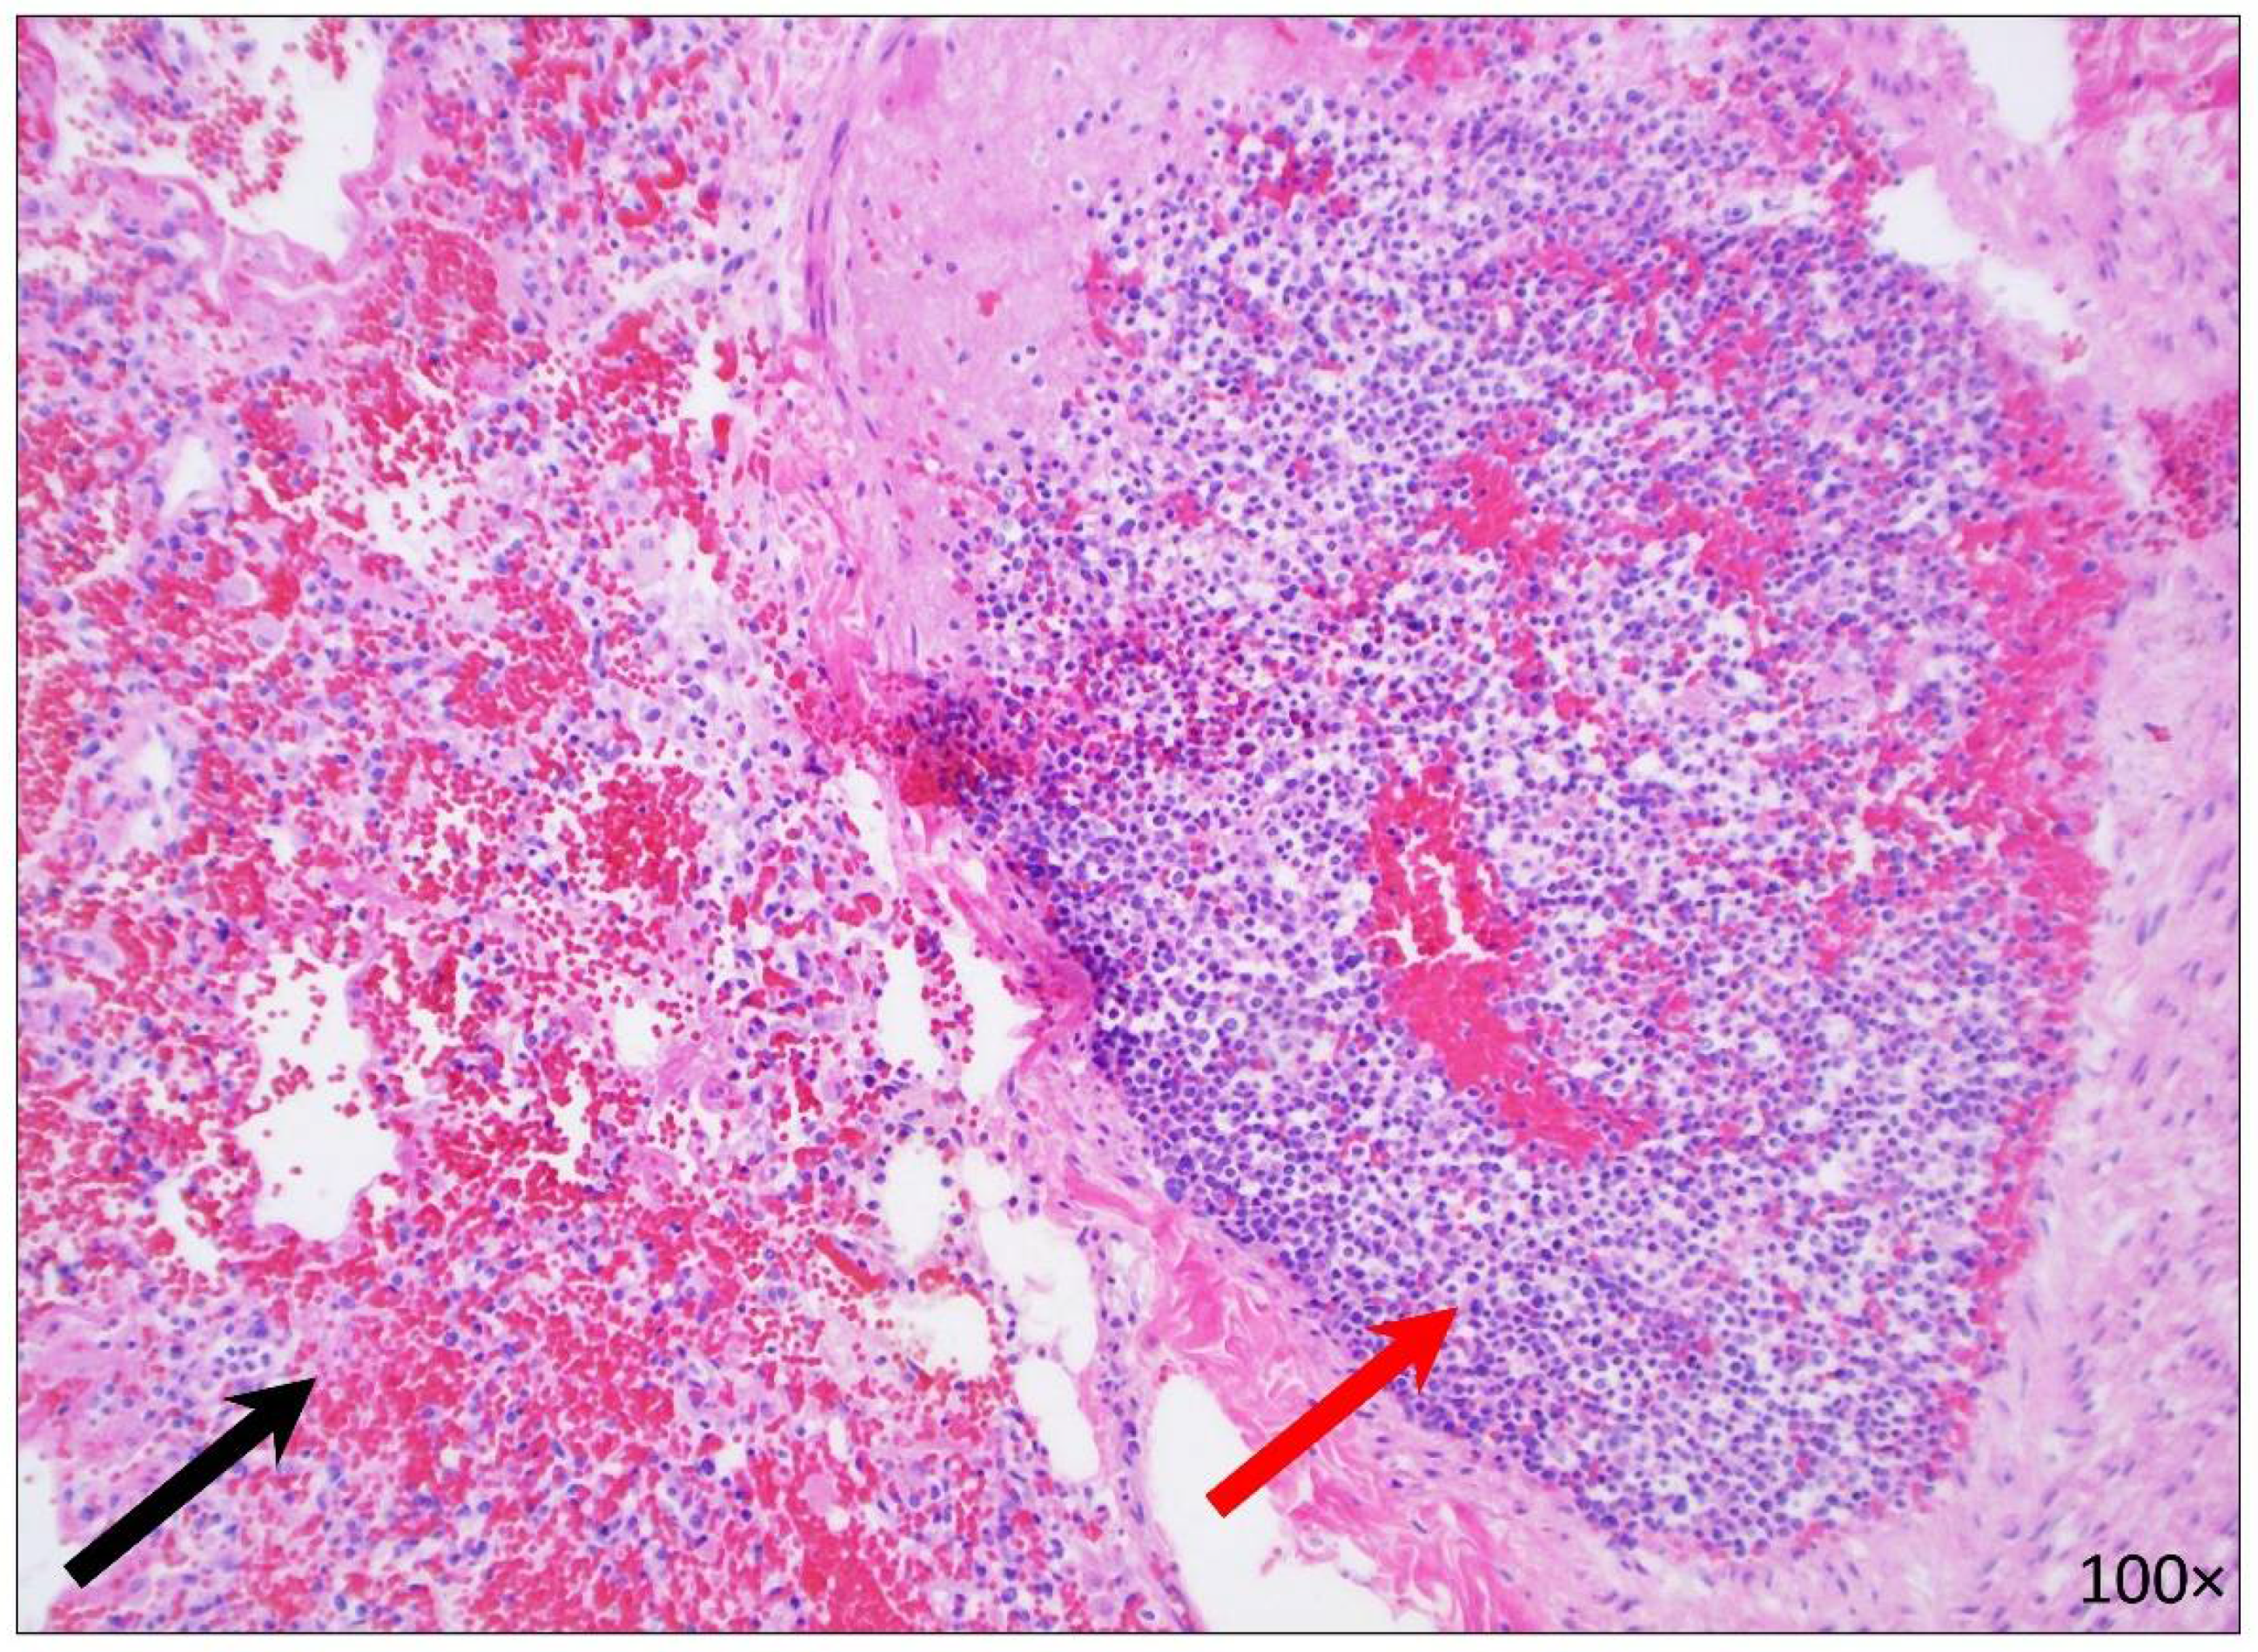

2.2.5. Hematopoietic System